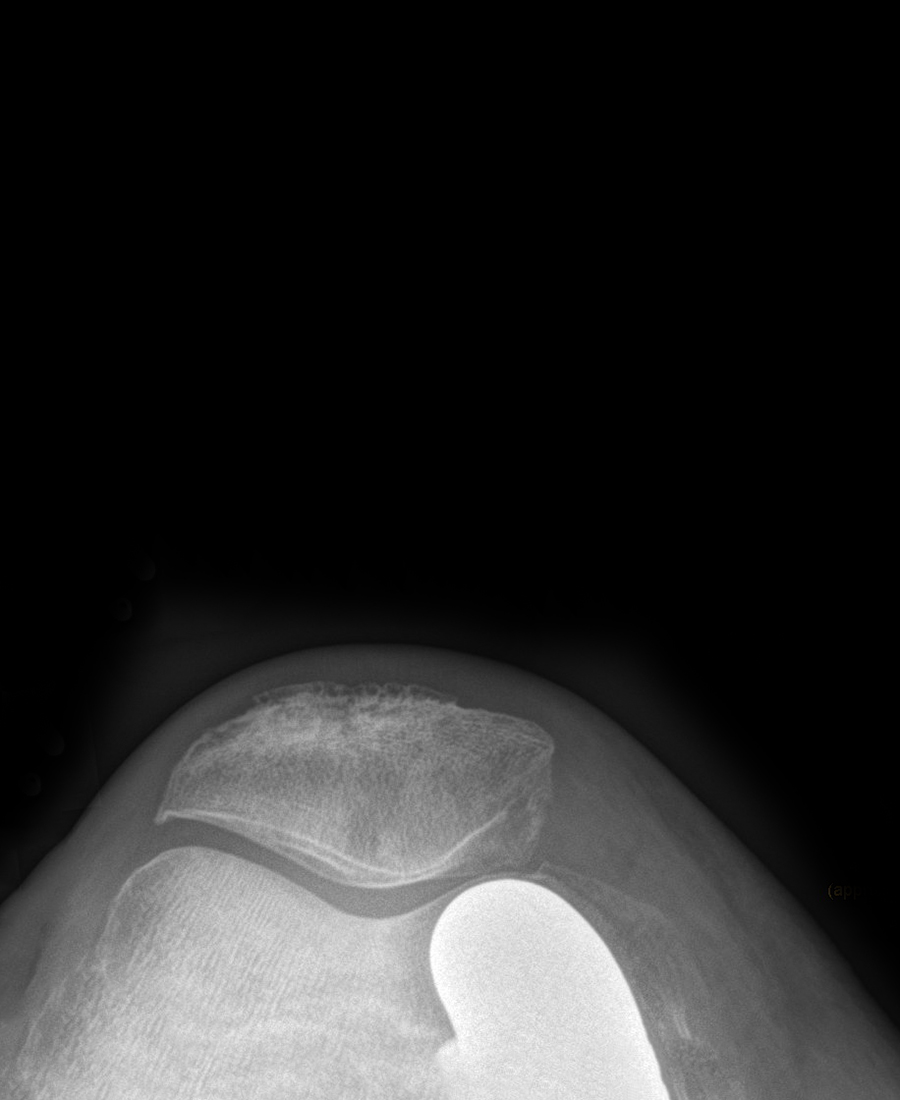

- Fortgeschrittene Kniearthrose (Gonarthrose)

- Rheumatoide Arthritis des Kniegelenks

- Schwere Verletzungen (posttraumatische Arthrose)

- Knochennekrose (Osteonekrose)

- Achsfehlstellungen (X-Bein, O-Bein)

Eine Knie-TEP wird empfohlen, wenn konservative Behandlungen (Medikamente, Physiotherapie, Injektionen, Orthesen) nicht mehr ausreichend helfen und Sie unter anhaltenden Schmerzen sowie deutlichen Bewegungseinschränkungen im Alltag leiden. Typische Indikationen sind fortgeschrittene Arthrose (Gonarthrose), rheumatoide Arthritis, posttraumatische Arthrose oder Knochennekrose.

- Teilprothese (Schlittenprothese/unikondyläre Prothese): Ersetzt nur den geschädigten Teil des Kniegelenks (medial oder lateral). Geeignet bei isoliertem Kompartmentschaden mit intakten Bändern.

- Vollprothese (Totalendoprothese): Ersetzt alle drei Gelenkkompartimente. Notwendig bei fortgeschrittener Arthrose in mehreren Bereichen.